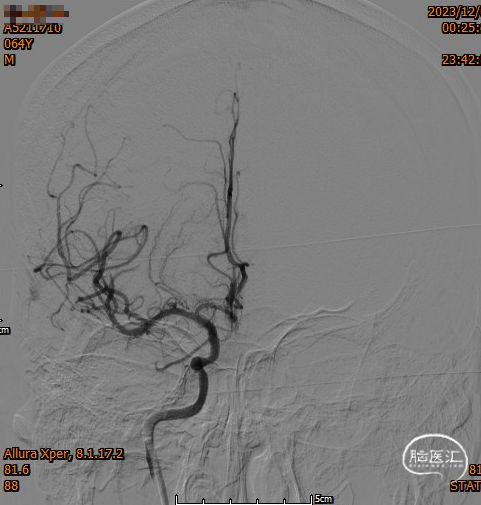

头颈部CTA

DSA

造影,颈内动脉未见血栓,颅内动脉较前未见明显减少,无明显血栓逃逸。

复查造影支架成形良好,颅内较前无明显改变,未发现血管减少影像,供血较前明显改善。